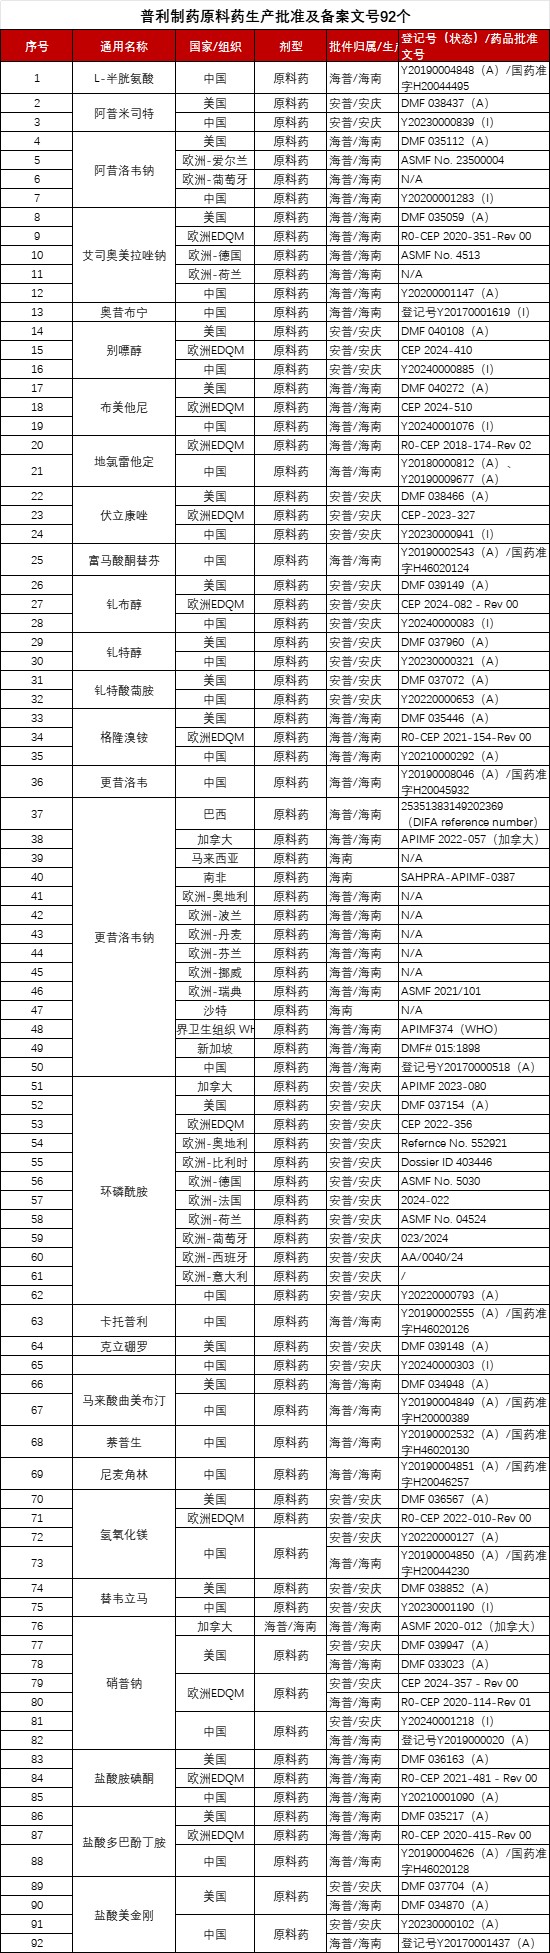

另外,普利制药已取得专利技术110余项,其中发明专利90余项;产品批准文号340余个,原料药生产批准及备案文号92个,药用辅料生产批准及备案文号15个,其中多款原料药和要用辅料也都通过了美国FDA与欧盟的认证。